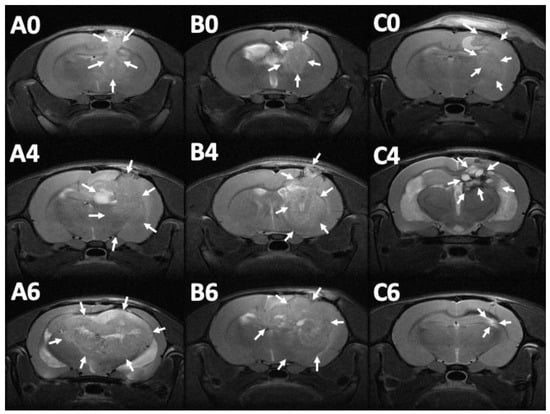

MRI images (T1- and T2-weighted) were obtained 12–14 days after injection of the F98 tumor cells into the cerebral parenchyma of rats, to confirm the successful creation of brain MG models. Serial brain MRI scans were obtained before treatment (0 day) and at 1, 2, 4, 6, and 8 weeks after treatment, in the three groups. Figure 8 shows the serial brain MRI scans of MG-bearing rats in the different therapeutic groups.

Figure 8.

Serial magnetic resonance imaging. The label in the upper-left corner of each image denotes the number of posttreatment weeks. No significant primary discrepancy was noted among the brain tumors in groups A (A0), B (B0), and C (C0). The tumor in groups A and B increased promptly with an obvious mass effect. A rigorous midline shift with bilateral ventricle affection was found in group A (A4 and A6). The tumor expanded inwardly (B4) then traversed the midline (B6). The tumor size reduced gradually in group C, after injection of SMPs (C4 and C6), while no perifocal edema was noticed (the tumor areas are indicated by white arrows).

The brain tumor volumes increased rapidly in group A (injected with pure PLGA microparticles group). More than half of the rats (7/13) died in week 4, and the maximum tumor volume was 589.92 × 10−3 mm3 in the only surviving rat in week 8. In group B (treated with the Gliadel wafer), the mean tumor volume was 60.26 ± 15.75 and 62.43 ± 17.01 × 10−3 mm3 before treatment and at 1 week posttreatment, respectively. The tumor volume almost did not increase during the first week. Subsequently, the tumor enlarged rapidly and reached its maximum (319.08 ± 105.92 × 10−3 mm3) at week 6; 75% of the rats (9/12) died in week 8. Due to the death of rats with large brain tumors, the mean brain tumor volume of the remaining three rats in group B was only 305.84 ± 138.02 × 10−3 mm3. In group C (treatment with SMP injection), the mean tumor volume was 56.73 ± 13.00 × 10−3 mm3 before treatment, and slightly decreased to 52.89 ± 29.05 × 10−3 mm3 after 1 week, but the difference was nonsignificant. The tumor volume increased slightly and reached its maximum (111.47 ± 112.93 × 10−3 mm3) at week 4. The mean tumor volume decreased progressively after week 4, being 109.28 ± 122.66 and 73.14 ± 94.44 × 10−3 mm3 at weeks 6 and 8, respectively. The difference in tumor volume between week 0 and week 2 was nonsignificant (p = 0.74). Figure 9 shows the results of using a repeated-measures mixed model to evaluate the mean brain tumor volume of the three groups. Significant differences were discovered between groups A and C and between groups B and C (both p < 0.001). Nevertheless, no significant difference was found between groups A and B (p = 0.4).